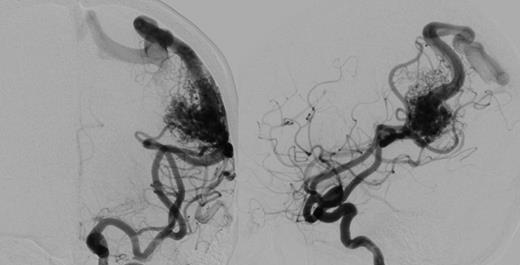

A 56-year-old female presented following a single tonic clonic seizure. Neurological examination was unremarkable. An MRI scan revealed a left posterior frontal parafalcine meningioma with vasogenic oedema in the precentral gyrus with a localized mass effect. In addition, there was a 2.6-cm left parietal AVM located in the left angular/supramarginal gyrus (Fig. 1). There was no evidence of prior haemorrhage. Cerebral angiography confirmed the arterial supply to be predominantly from enlarged parietal and angular branches of the left middle cerebral artery. Venous drainage was superficial into an enlarged vein of Trolard towards the superior sagittal sinus (Fig. 2).

Axial T1-weighted gadolinium-enhanced MRI showing a 2.6-cm left parietal AVM located in the left angular/supramarginal gyrus (left) and an enhancing posterior frontal parafalcine meningioma in close association with the superficial draining veins of the AVM.

Cerebral angiogram, antero-posterior (left) and lateral (right) revealing a 2.6 × 2.6 × 3.4 cm sulcal type AVM in the left parietal region. Arterial supply is from enlarged parietal and angular branches of the left middle cerebral artery. Venous drainage is superficial into an enlarged vein of Trolard towards the superior sagittal sinus.